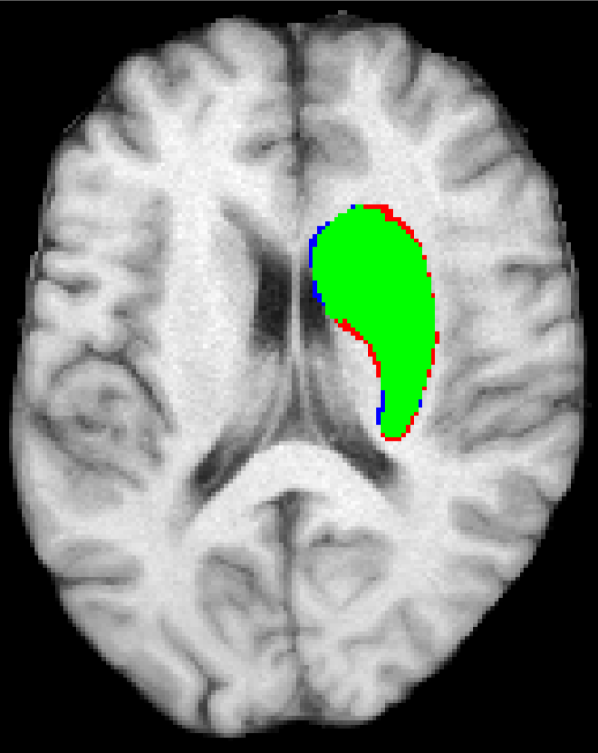

Representative examples of the qualitative results from the proposed method can be found in Figure 4. Cases 9 and 15 represent the overall results of the proposed methodology, correctly detecting the lesions in most cases with an outline that approximates the provided gold standard. Among the observed limitations are inaccurate borders and over/under segmentation of certain regions. For instance, in case 5 the lesion was undersegmented due to a heterogeneous appearance of the gold standard lesion while in case 13 two false positive lesions are detected due to the previous existence of chronic stroke lesions with a similar appearance.

Refer to caption

(a) Case 5

(b) Case 9

(c) Case 13

(d) Case 15

Figure 4: Output segmentation masks of representative cases from the training images of ISLES 2015 SISS dataset. On all images, true positives are denoted in green, false positives in red and false negatives in blue.